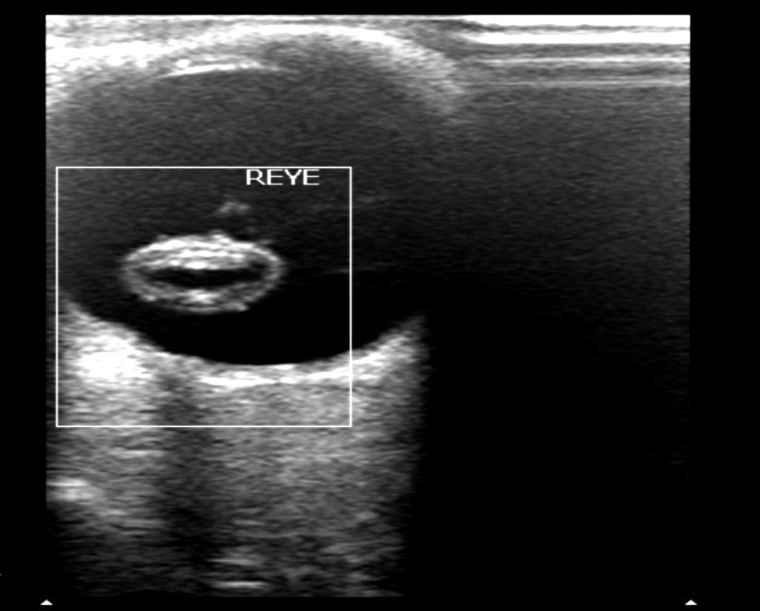

彩色多普勒检测:环状结构内无血流信号(图 7 )。

图 7 晶状体全脱位彩色多普勒超声表现

图片来源:作者提供